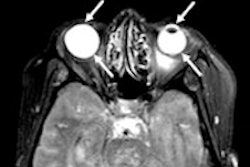

Researchers have made available a collection of 304 T1-weighted MR images so that their counterparts worldwide can develop algorithms to better evaluate stroke patients and personalize treatment. The international group described the work in a study published online February 20 in Scientific Data.

The open-source dataset is known as the Anatomical Tracings of Lesions After Stroke (ATLAS). Through this resource of manually segmented lesions and metadata, the researchers hope to identify biological markers that could predict which rehabilitation therapies will produce the best response.

"One of our goals is to meta-analyze thousands of stroke MRIs from around the world to understand how the lesions impact recovery," said lead author Sook-Lei Liew, PhD, an assistant professor at the University of Southern California (USC), in a release from the university. "We are really interested in helping find better automated ways, using machine learning and computer vision, to identify the lesions and have machines draw those boundaries."